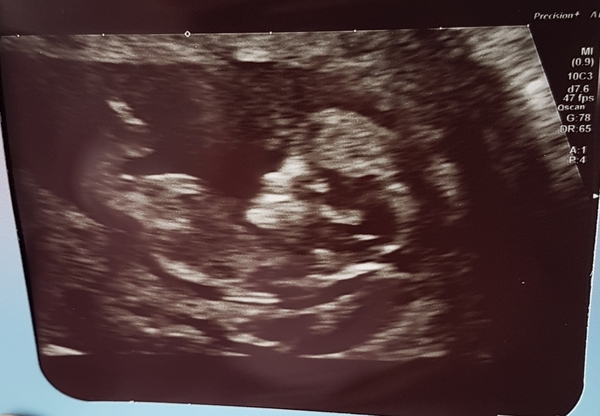

I'm now 12 weeks so I feel a bit more comfortable posting now, hope it's ok to share my scan.

Big massive congrats to you June, this bit is my favourite. Tiring but just so lovely. And to Aph too, great scan pic there.